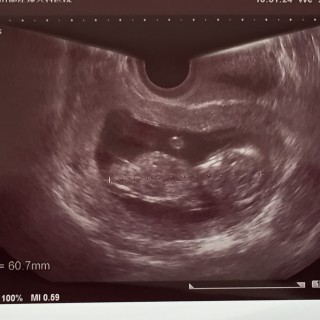

1ヶ月振りの健診。つわりもあまりなく、ちゃんと育っているか不安はあったけどエコーを見て安心。流産の兆候もなく元気に育っているそう!手足も動かしてて感動…っ!CRLは64.9mmでしたー!次も1ヶ月後の健診なので、どれくらい成長しているか楽しみ~

6.25cmになりました~! 首の後ろのむくみもなく、順調に育っているようです。鼻の骨も出来て、目も出来てました。 旦那サマも一緒に妊婦検診に参加し、動く赤ちゃんを初めて見ました。感動してくれたようで良かった♪